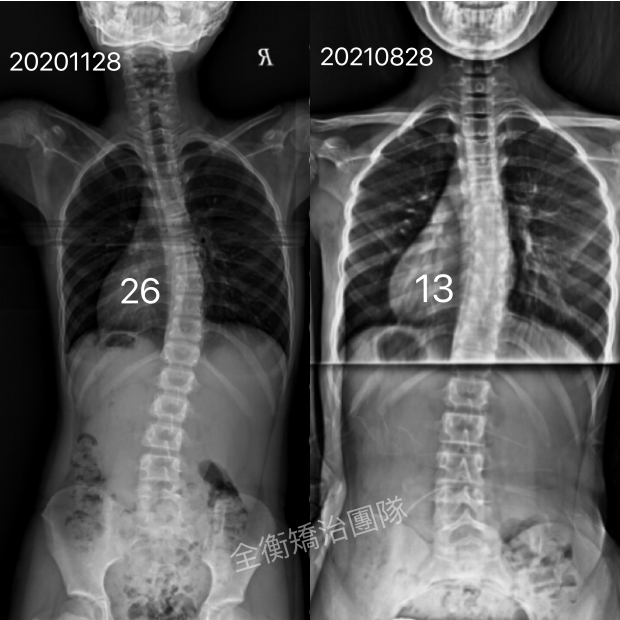

13嵗側彎女生持續追蹤,成果穩固:脊椎側彎矯正後效果可以維持多久?13嵗側彎女生持續追蹤,成果穩固:脊椎側彎矯正後效果可以維持多久?

「脊椎側彎矯正的成效,能夠在療程結束後持續存在嗎?」

「停止治療後側彎度數是否又會慢慢增加回來?」 -